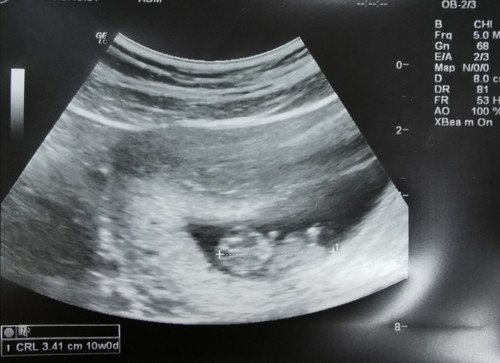

วันนี้ไปงานเปิดตัวนมเอนฟาโกร เอนฟินิทัสมาค่ะ ได้ความรู้เรื่องสารอาหารในนมแม่มาเพียบ เวลาผ่านไปเร็วมาก ในงานวันนี้เปิดตัว เอนฟาโกร เอภูมิคุ้มกันที่ดีที่สุด เป็นสูตรใหม่ที่มีแลคโตเฟอร์รินสารอาหารที่พบในน้ำนมเหลืองหรือนมแม่ที่ไหลออกมาเป็นสีเหลืองช่วงวันแรกๆหลังคลอดนั่นเองค่ะ ซึ่งคุณหมอบอกว่าแลคโตเฟอร์รินเนี่ยเป็นตัวช่วยเสริมภูมิคุ้มกันของลูกโดยเฉพาะ ช่วยต่อต้านเชื้อโรคต่างๆ ทำให้ลูกแข็งแรง ไม่ป่วยบ่อย ช่วงโควิดทำให้เรารู้ว่าภูมิคุ้มกันสำคัญกับเรามากแค่ไหน มาเสริมภูมิคุ้มกันให้ลูกเตรียมไว้ก่อนค่ะแม่ เพราะไม่รู้เลยว่าจะมีอะไรเกิดขึ้นอีก😅 #เอนฟาโกรเอนฟินิทัส #แลคโตเฟอร์รินพบมากในน้ำนมเหลือง #สูตรที่ดีที่สุดจากเอนฟา #ภูมิคุ้มกันที่ดีที่สุด